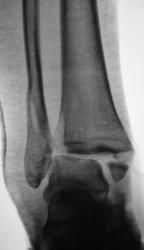

Пол пациента: Мужской пол Тип патологии: Травма Область исследования: Скелетно-мышечная система Методы исследования: Rg Пациенту в ургентном порядке был произведен "первичный снимок". Сегодня пациента доставили на "контрольный снимок". Какие мнения будут уважаемые коллеги? 1.REp_..jpg 2.REp_..jpg 3.REp_..jpg 4.REp_.jpg ВложениеРазмер 1.REp_..jpg70.64 КБ 2.REp_..jpg90.44 КБ 3.REp_..jpg84.75 КБ 4.REp_.jpg72.61 КБ Ср, 09/12/2009 - 20:21 #1 Иринка Не на сайте Был на сайте: 11 лет 5 месяцев назад Зарегистрирован: 16.11.2009 - 22:14 Публикации: 190 Трёхлодыжечный перелом с разрывом дистального межберцового синдесмоза и подвывихом стопы кнаружи. Репозиция неудовлетворительная, показано оперативное лечение. Ср, 09/12/2009 - 20:25 #2 v1tal Не на сайте Был на сайте: 4 года 9 месяцев назад Зарегистрирован: 07.06.2008 - 19:41 Публикации: 1779 На оперативное разрешение все "бонусы" собраны. "Знаешь, у некоторых врачей есть комплекс мессии — им необходимо спасать мир. А у тебя комплекс Рубика — тебе необходимо решать головоломки."

Трёхлодыжечный перелом с разрывом дистального межберцового синдесмоза и подвывихом стопы кнаружи. Репозиция неудовлетворительная, показано оперативное лечение.